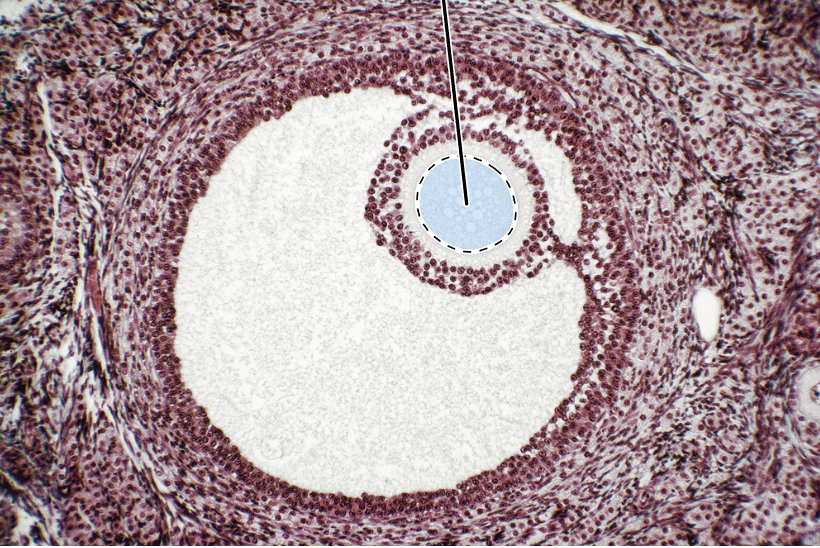

ovary (mature tertiary follicles)

oocyte

zona pellucida

granulosa cells

theca interna

corona radiata

antrum